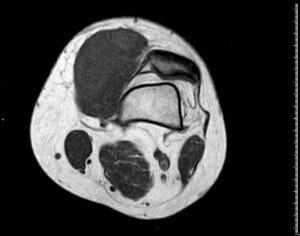

RM T1 con supresión grasa y contraste IV

HALLAZGOS RADIOLÓGICOS